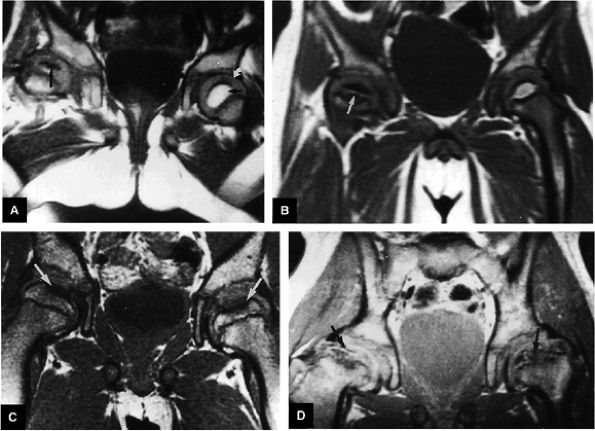

FIGURE 3.80 ● Extended pattern of marrow edema in association with osteonecrosis. Edema of the femoral neck is hypointense on T1-weighted image (A) and hyperintense on FS PD FSE image (B). (C, D) A separate case of AVN with an ischemic focus demonstrating attenuated fat signal with adjacent reactive femoral head and neck edema. The marrow edema does not extend into the ischemic region. (C) Coronal T1-weighted image. (D) Coronal FS PD FSE image.